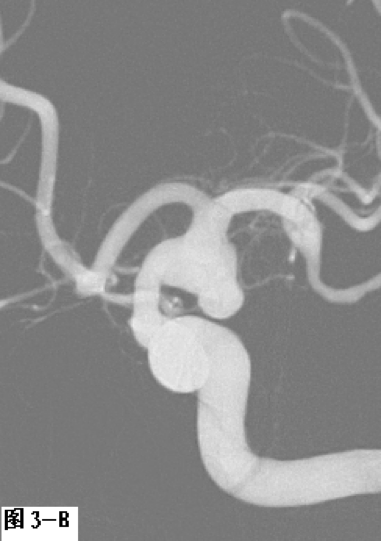

图3 采用支架辅助双微导管技术栓塞左侧颈内动脉后交通段不规则形态动脉瘤。A.DSA显示囊性动脉瘤破裂后在瘤体顶端又形成一假性动脉瘤;B.工作角度发现该动脉瘤瘤颈宽,颈内动脉直接成为瘤颈一部分;C.在部分释放支架情况下,交替填塞微弹簧圈;D.动脉瘤填塞致密,载瘤动脉通畅。